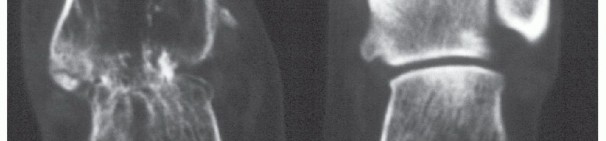

If the patient is not on steroids and is in reasonable health, a revision arthrodesis is attempted. The docking site is explored, and fibrous tissue is removed. The bone surfaces are revised to bleeding bone (FIG 6).

The mobile nonunion forms a pseudojoint similar to fascial arthroplasty that allows them to walk independently (FIG 7).

We have observed four patients who have maintained this pseudojoint for years and are able to participate in activities of daily living.

FIG 7 • A,B. Bilateral tibiocalcaneal arthrodesis nonunion after failed infected ankle arthrodesis and infected total ankle arthroplasty. The patient is on high doses of steroid medication. The infections were eradicated. C. Clinical photograph of bilateral tibiocalcaneal nonunion with fibrous pseudojoint. Observe the free flap on the medial ankle. The patient uses a scooter for traveling distances but can walk independently and is independent in activities of daily living.